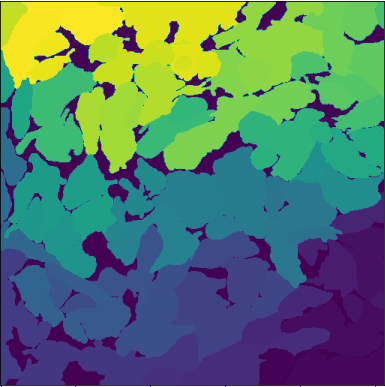

Stratifying the data by the six projection methods (Figure 2) linked abnormally high BRISQUE values to images processed with PDP. These images also showed generally higher PIQE and NIQE scores than the other techniques. Qualitative inspection of images with the worst BRISQUE scores confirmed corruption (Figure 3(c)). As a result, PDP images were unusable for GT annotation and were discarded from further analysis.

Given the large number of outliers in the box-plot analysis shown in Figure 2, we prioritized the median over the mean to select an optimal projection method for frames fusion and image quality enhancement on the HL-1 dataset. Overall, SP and AP performed best on PIQE and BRISQUE, yielding the lowest median values (PIQESP, PIQEAP = 5.03; BRISQUESP, BRISQUEAP = 12.08), with the minimum BRISQUE score (-13.86) found in the AP group (Figure 2). SP and AP images showed similar performance patterns (mean, median, and distributions) across all three NR-IQA metrics (Figure 2), indicating comparable behaviour on the HL-1 dataset. However, independent paired t-tests and effect-size analyses across PIQE, NIQE, and BRISQUE (available in [16]) revealed several statistically significant differences and high effect sizes between SP and AP for some preprocessing-projection method combinations. Thus, while similar, these methods are not fully interchangeable and should both be considered for downstream analysis.

QP, directly followed by SDP, were associated with the lowest median NIQE scores (i.e., NIQEQP = 14.55, NIQESDP = 15.01), despite demonstrating a lower performance than SP and AP methods based on PIQE and BRISQUE scores. Finally, images processed using MIP were associated with lower quality scores across all metrics compared to SP, AP, QP and SDP.